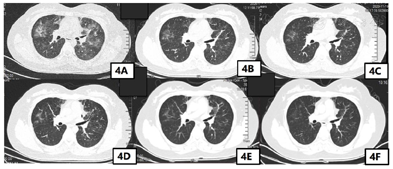

患者糖皮质激素停药后8 d,2020年10月29日患者再次出现胸部不适,通气不畅,吸入冷空气可诱发咳嗽,1 d后再次出现行走后呼吸费力及胸痛,患者急诊返院。完善胸部CT提示双肺多叶、段磨玻璃密度斑片影范围较前增大、密度较前增高(图4)。患者已完成糖皮质激素治疗,停药后再次出现目前免疫检查点抑制剂相关肺炎症状,因患者病情复杂,完善多学科疑难病例会诊,影像科会诊意见患者目前CT提示肺部以对称性、渗出性病变为主,纤维化不重,暂无间质性改变。此种肺部影像学变化常为过敏反应,药物反应及肺水肿,此患者考虑与药物性肺炎有关。目前患者病情反弹,考虑激素依赖,建议密切复查肺部HRCT。呼吸科会诊意见考虑免疫治疗相关肺不良反应可能性大,不除外过敏性肺泡炎。建议停用免疫治疗,复查总IGE及过敏原检查,变态反应原除外过敏反应。患者目前症状反复与糖皮质激素剂量有关,可适当延长糖皮质激素使用时间,建议复查结核相关检查。感染科会诊意见患者目前CRP、降钙素原不高,COVID19核酸多次监测阴性,不考虑细菌性肺炎,可行巨细胞病毒IGm、IGg,病毒载量及EBV病毒IGm、IGg,病毒载量检查及呼吸道病毒检测(痰液)除外病毒性感染,风湿科会诊意见密切复查肺CT,找到合适激素剂量维持,不除外药物反应,如药物延迟超敏反应。如患者症状持续进展,建议可上级医院会诊治疗,建议完善铁蛋白,总IgE,ANA,红细胞沉降率,大小系列,白介素,淋巴计数等检查。患者上述检查均无明显异常,综合会诊意见,考虑患者症状再发原因是激素依赖型,既往激素治疗过程中激素减量较快,继续予患者糖皮质激素治疗,此次需延长糖皮质激素治疗时间,缓慢减少糖皮质激素用量。2020年10月30日—2020年11月5日予美卓乐8片口服(32 mg=泼尼松的等效剂量40 mg),2020年11月6日—2020年11月12日予美卓乐6片口服(24 mg=泼尼松的等效剂量30 mg),2020年11月13日—2020年11月19日予美卓乐5片口服(20 mg=泼尼松的等效剂量25 mg),2020年11月20日—2020年11月26日予美卓乐4片口服(16 mg=泼尼松的等效剂量20 mg),2020年11月27日—2020年12月3日予美卓乐3片口服(12 mg=泼尼松的等效剂量15 mg),2020年12月4日—2020年12月10日予美卓乐3片与2片交替口服,2020年12月11日—2020年12月17日予美卓乐2片口服(8 mg=泼尼松的等效剂量10 mg),2020年12月18日—2020年12月24日予美卓乐2片与1片交替口服,2020年12月25日—2021年1月7日予美卓乐1片口服(4 mg=泼尼松的等效剂量5 mg),本次共使用糖皮质激素治疗10周。患者第2次糖皮质激素治疗后出现较严重副作用,包括水潴留,周身水肿,激素患者减量至美卓乐1片时患者仍需利尿剂治疗,皮质功能亢进综合征,体重增加(由激素治疗前65 kg增至68 kg),腹泻(诺如病毒感染)及便真菌感染,均予对症治疗。

患者的第2次激素治疗后症状完全缓解,复查胸部CT肺部斑片影基本消失(图4)。第2次激素停药后长期随访无再发免疫检查点抑制剂相关性肺炎症状,免疫检查点抑制剂相关性肺炎治愈。